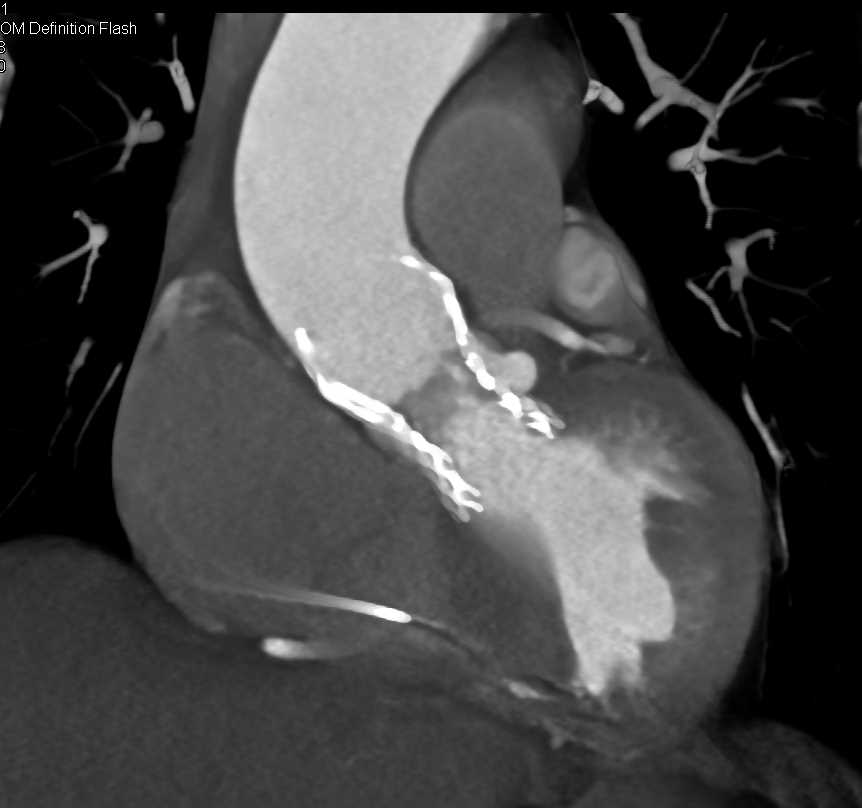

Post Transcatheter Aortic Valve Replacement (TAVR) Changes Aortic Valve